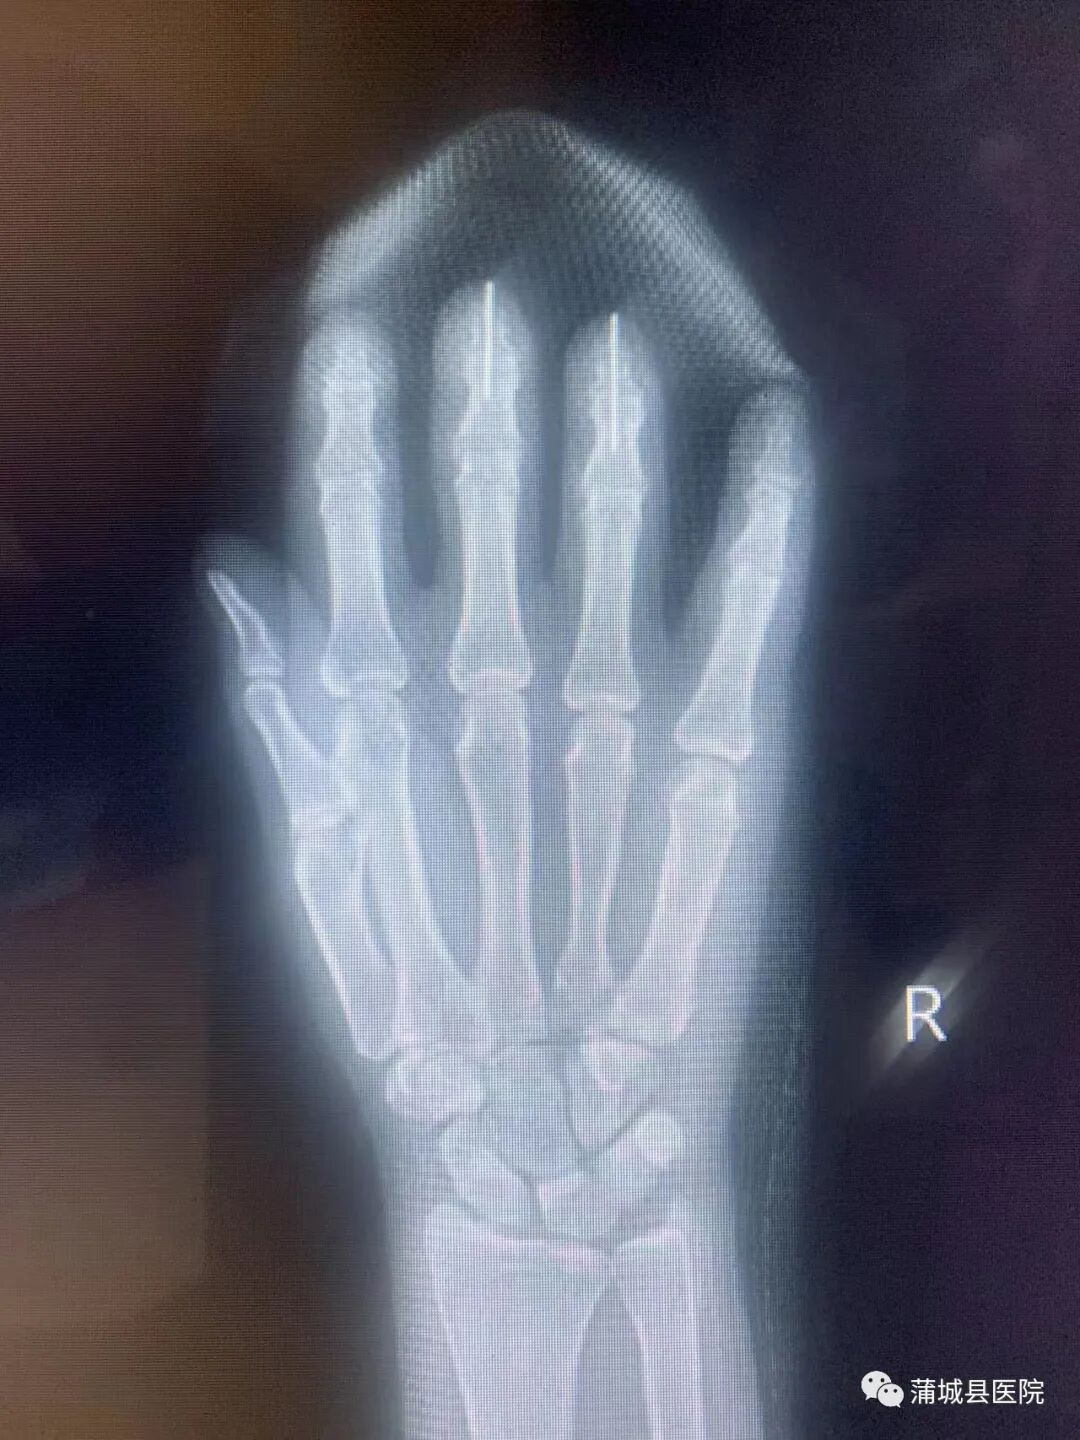

(术后X光片)